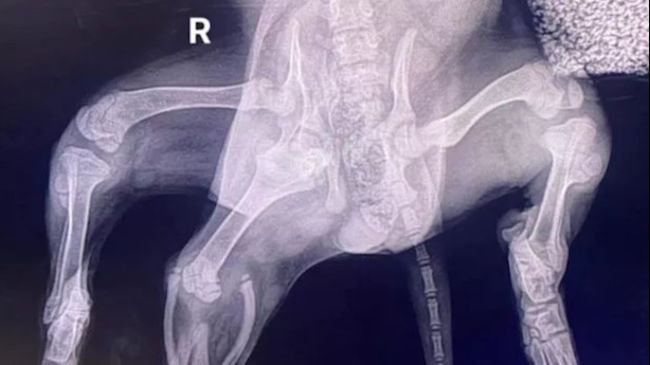

Her partially joined extra rear legs resembled a mermaid’s tail, hence her the name, which is derived from Disney’s Little Mermaid.

A spokesman for the charity said: “Her additional limbs have been removed. Thankfully having the CT images meant they did not discover anything unexpected and although it wasn’t a regular amputation it was ‘uneventful’.

After an examination, the puppy appeared to have two extra legs and two vulvas – despite being in reasonable condition.Credit: Greenacres Rescue/Media Wales